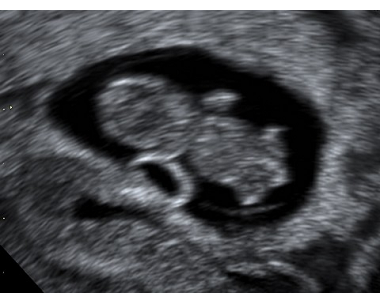

3D ultrazvuk plodu ve stáří 9+2.

Autoři: Texty na základě zdroje www.babyonline.cz, vlastní praxe a znalostí zpracovala MUDr. Jarmila Halová, doplnil a upravil MUDr. Ondřej Šimetka, přednosta Porodnicko-gynekologické kliniky FN Ostrava, kde byl rovněž pořízen ultrazvukový obrázek, autor: MUDr. M. Pětroš. Poslední korekturu v srpnu 2024 provedla: MUDr. Veronika Ťápalová (Gynekologicko-porodnická klinika LF MU a FN Brno).